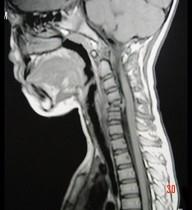

问题 男,37岁,主诉颈部疼痛,活动时加重,休息后疼痛可减轻,夜间盗汗等,请结合所提供图像,选出最佳答案 ( )

选项 A、颈椎结核 B、骨髓瘤 C、颈椎骨转移 D、颈椎退行性变 E、骨巨细胞瘤

答案 A